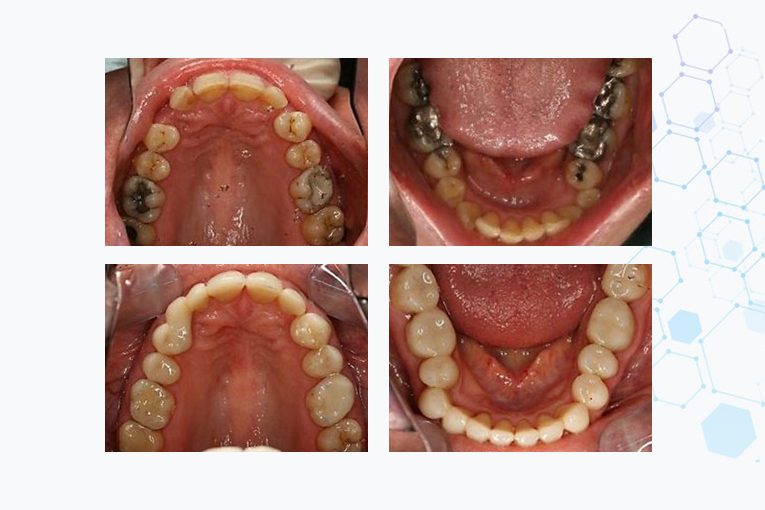

Replacement of all old amalgam fillings with composite as part of full mouth reconstruction.

Large carious lesions restored with composite.

Amalgam fillings are removed here and replaced with composite.